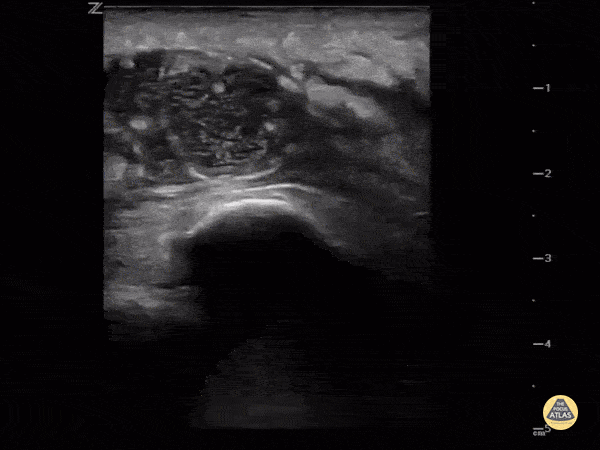

Sometimes it's hard to tell if the knee is septic or just the bursa. Ultrasound can help. This image demonstrates a hypoechoic fluid collection ABOVE the patella consistent with pre-patellar bursitis. Image courtesy of IUEM Ultrasound Original Twitter Post can be found here.